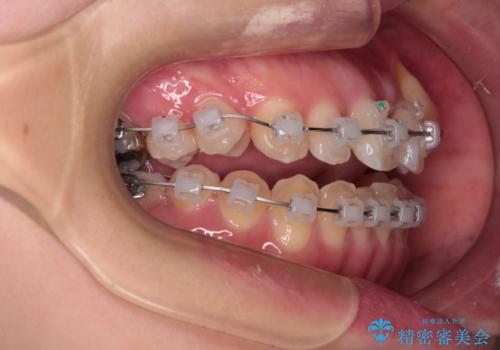

- クリアブラケット

- 上顎の八重歯やデコボコを気にして来院された患者様です。

上顎歯列が狭窄していたため、急速拡大装置により上顎骨を側方に拡大しながら、ワイヤー装置にて矯正治療を行うこととしました。

上顎骨を拡大することで、八重歯やデコボコを歯列に収めることができ、下顎の歯が外に位置していた奥歯の咬み合わせも改善することができました。

スペースも短期間に獲得できるため、1年程度で治療を終えることができました。